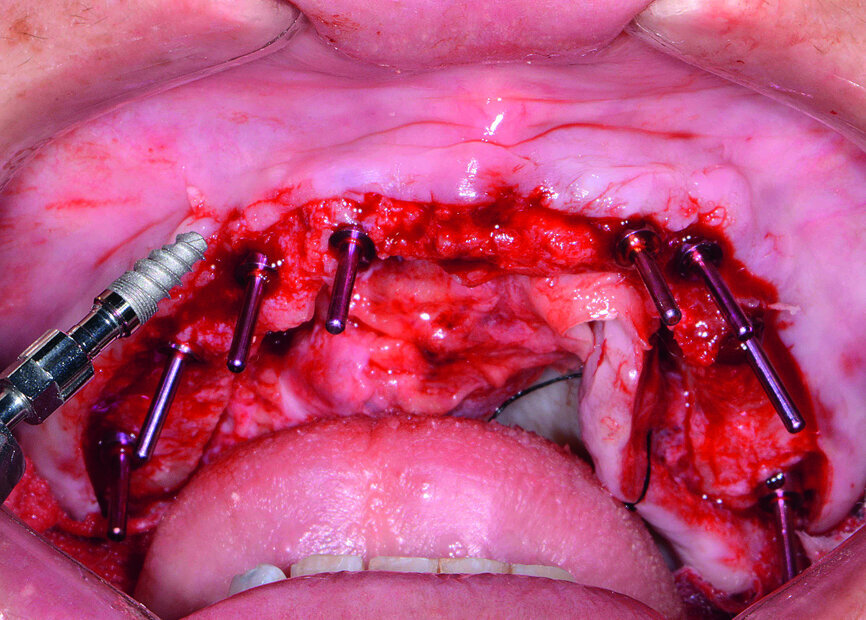

Fig. 10: Paralleling pins placed.

At the surgical appointment, intravenous sedation was administered to the patient. The bone-level surgical guide was seated over the patient’s maxilla once the tissue had been reflected, and the fixation pins were tightened (Fig. 9). The implant osteotomies were created following the simplified surgical protocol of the Hahn Tapered Implant System. Eight implants were placed from second molar to second molar in the maxillary arch (Figs. 10 & 11). Healing abutments were connected to the implants to help prepare the soft tissue for the restorative phase (Fig. 12).